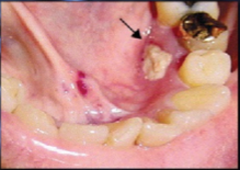

-Actinomyces israelii -draining abscesses with SULFUR GRANULES in the pus